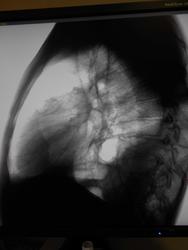

Пол пациента: Мужской пол Тип патологии: Другое Область исследования: Грудная клетка и верхние дыхательные пути Методы исследования: Rg Мужчина, 1983 года рождения, наркоман. Жалобы на затруднение дыхания, больше толком ничего не может сказать. Поставила просто показать, наверное это осумкованный плеврит, но очень уж форма причудливая) https://radiomed.ru/sites/default/files/styles/case_slider_image/public/user/16049/dscn0196-2.jpg?itok=VMOIZfz8 https://radiomed.ru/sites/default/files/styles/case_slider_image/public/user/16049/dscn0200-2.jpg?itok=jF8RVB_8 https://radiomed.ru/sites/default/files/styles/case_slider_image/public/user/16049/dscn0199-2.jpg?itok=d8mgQYPQ ID:25338 Пнд, 24/12/2012 - 21:04 #1 Катенёв Валенти... Не на сайте Был на сайте: 7 лет 2 недели назад Зарегистрирован: 22.03.2008 - 22:15 Публикации: 54876 Здравствуйте Мила! Задний паракостальный без сомнений! Пнд, 24/12/2012 - 23:58 #2 Наталия Васильевна Не на сайте Был на сайте: 5 лет 8 месяцев назад Зарегистрирован: 25.09.2011 - 09:02 Публикации: 754 Катенёв Валентин Львович wrote: Здравствуйте Мила! Задний паракостальный без сомнений! Согласна, вопрос как давно? Если процесс "свеженький"-может, пардон, шарахнуть в эмпиему в любой момент. Втр, 25/12/2012 - 01:11 #3 И.Бондаренко Не на сайте Был на сайте: 2 дня 13 часов назад Зарегистрирован: 13.09.2011 - 22:55 Публикации: 9206 Наталия Васильевна wrote: Катенёв Валентин Львович wrote: Здравствуйте Мила! Задний паракостальный без сомнений! Согласна, вопрос как давно? Если процесс "свеженький"-может, пардон, шарахнуть в эмпиему в любой момент. Пусть хирурги "шарахнут" пункцией. Тогда точно будете знать. Втр, 25/12/2012 - 03:06 #4 Mila85 Не на сайте Был на сайте: 3 года 1 месяц назад Зарегистрирован: 15.03.2012 - 16:59 Публикации: 1790 Катенёв Валентин Львович wrote: Здравствуйте Мила! Задний паракостальный без сомнений! Здравствуйте, мы на работе тоже так единогласно подумали. Давность неизвестна, пациент где-то частно наблюдается со своей зависимостью, туда и потопал

Задний паракостальный без сомнений!

Согласна, вопрос как давно? Если процесс "свеженький"-может, пардон, шарахнуть в эмпиему в любой момент.